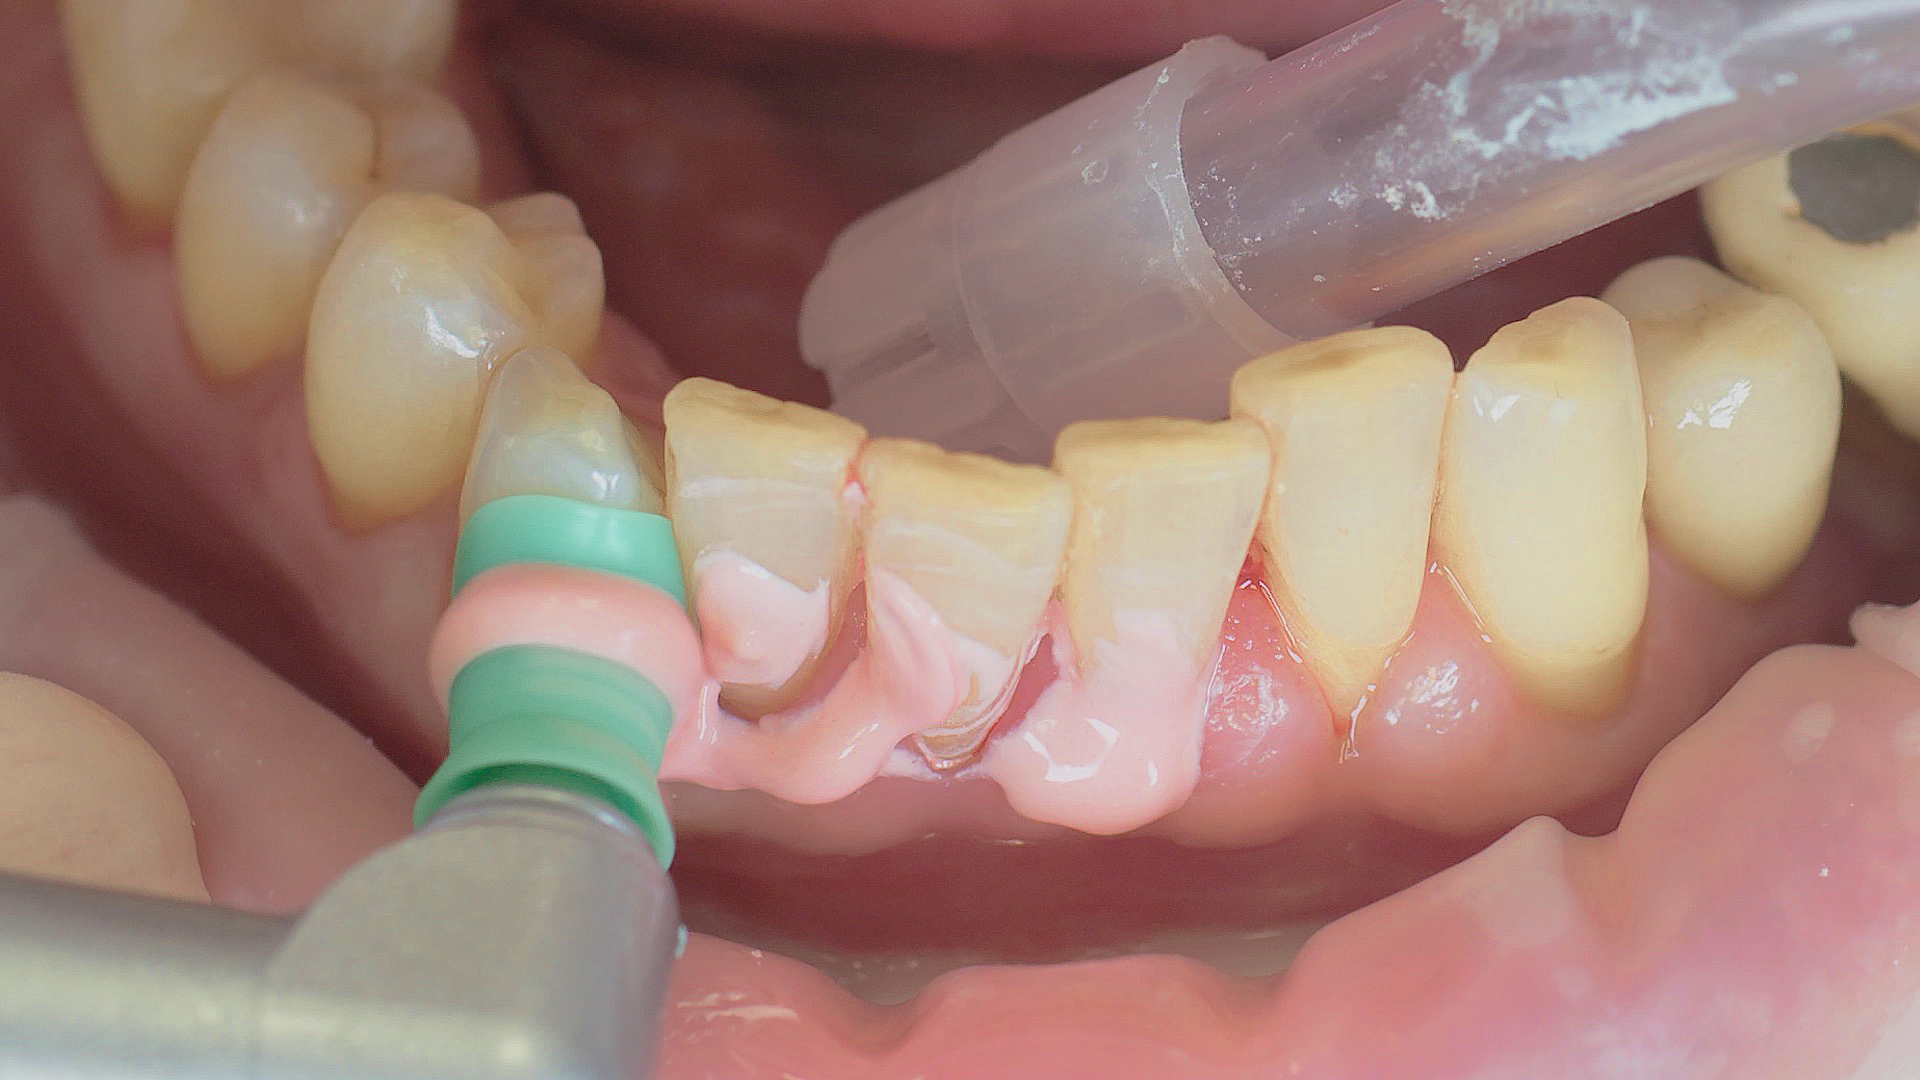

Where necessary, initial periodontal treatment is carried out. First, professional tooth cleaning establishes healthy gingival conditions. In this procedure, calculus (Fig. 1) and biofilm (Fig. 2) are removed as far as the gingival sulcus. In combination with careful instruction on oral hygiene, this gives the patient the basis for long-term freedom from inflammation.15

Removal of subgingival coatings (debridement) is carried out using sonic or ultrasonic devices and special periodontal tips as initial periodontal treatment (Fig. 3). Manual instruments can also be used. Further surgical and/or regenerative measures may be necessary, depending on the situation.